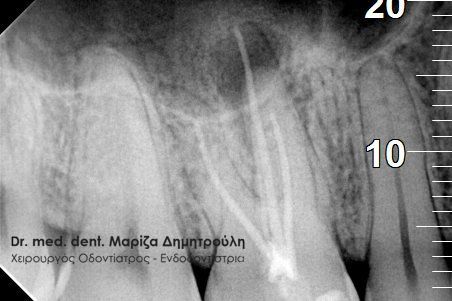

Η ασθενής προσήλθε με έντονο πόνο στο ιατρείο και είχε λάβει τις προηγούμενες μέρες αντιβίωση, εφόσον στην άνω αριστερή πλευρά της είχε οίδημα. Μετά την κλινική εξέταση διαπιστώθηκε η ύπαρξη ενός συριγγίου υπερώια μεταξύ των δύο άνω αριστερών γομφίων. Πραγματοποιήθηκε ακτινογραφία με την τοποθέτηση ενός κώνου γουταπέρκας για τη διάγνωση του υπαίτιου δοντιού, που είχε προκαλέσει την εμφάνιση του συριγγίου. Σύμφωνα με όσα αποκάλυψαν η κλινική και ακτινογραφική εξέταση ακολούθησε η έναρξη απονεύρωσης στο δεύτερο άνω αριστερό γομφίο, δεδομένου οτι είχε ένα βαθύ λευκό σφράγισμα ρητίνης που εκτεινόταν στο ύψος του νεύρου του δοντιού. Το δόντι είχε έντονα συμπτώματα πόνου κατά την επίκρουσή του.

Μετά την ολοκλήρωση της απονεύρωσης στο δεύτερο άνω αριστερό γομφίο το δόντι είναι ασυμπτωματικό. Η αποκατάσταση του δοντιού πραγματοποιήθηκε με λευκό σφράγισμα ρητίνης, εφόσον το έλλειμμα των οδοντικών ιστών ήταν μικρό και δε χρειαζόταν η προστασία του δοντιού με θήκη / στεφάνη δοντιού.

Σε δεύτερη φάση θα ακολουθήσει η επανάληψη απονεύρωσης στον πρώτο άνω αριστερό γομφίο, καθώς η απονεύρωση του δεν καλύπτει όλο το μήκος των ριζών του δοντιού και το δόντι μετά το πέρας της ενδοδοντικής θεραπείας συνεχίζει να πονά.

ΠΡΙΝ

ΜΕΤΑ